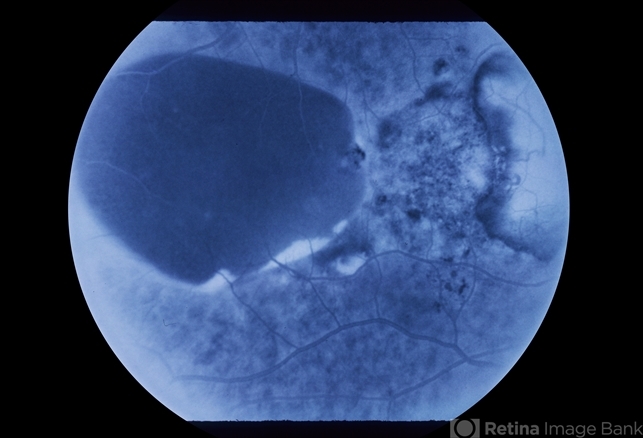

52 year old caucasian emmotropic female with long term follow-up of presenile macular degeneration.